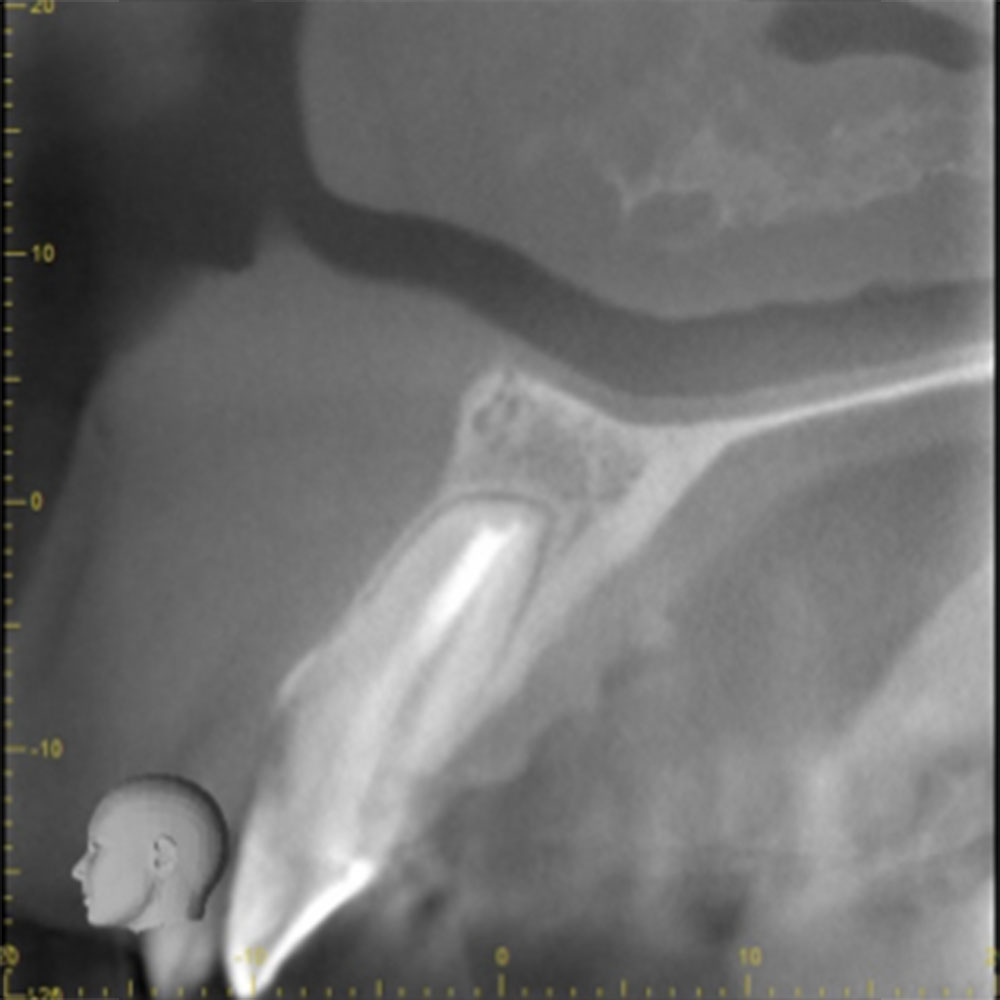

こちらは虫歯で神経を取らないといけなくなりましたが、何度治療しても痛みが消えないと言うことで当院にいらっしゃいました。度重なる治療で歯の神経のあった場所がかなりひろげられており、また根の先端も破壊されている状態でした。ですので、痛みが消えないのです。

肉眼では根の先端は見ることができませんがマイクロスコープでは見ることができます。根の先端をこれ以上破壊しないように清掃して歯の神経があった場所にお薬を詰めることができました。根の治療後、かぶせ物までして半年たっても痛みがありません。

レントゲンを見ていただいて、歯の先までしっかり白いお薬が入っているのがわかります。